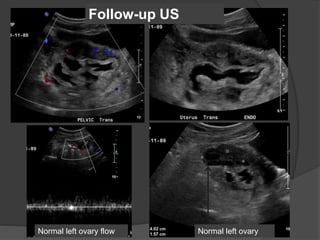

Follow-up US

Case 2: 12 year old female with abdominal pain

Dilated fallopian tube with thickened and enhancing tubal wall

Right

ovary

Complex

tubular

mass

Normal left ovaryNormal left ovary flow

Diagnosis: Torsion of the left Fallopian tube

Dilated tube with thickened, echogenic walls

and absence of vascular flow in the tube